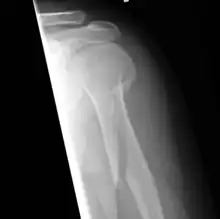

A spiral fracture (a.k.a. torsion fracture) is a bone fracture occurring when torque (a rotating force) is applied along the axis of a bone.[1] Spiral fractures often occur when the body is in motion while one extremity is planted. For example, a spiral fracture of the tibia (the shinbone) can occur in young children when they fall short on an extended leg while jumping. This occurrence is known as "toddler's fracture". Spiral fractures are also recognized as being suspicious in very young children since to obtain a fracture of this sort requires forceful twisting or jerking of the limbs. Child abuse (physical abuse) and certain conditions such as osteogenesis imperfecta (OI) are considered differentials when identifying spiral or torsion fractures.[2]